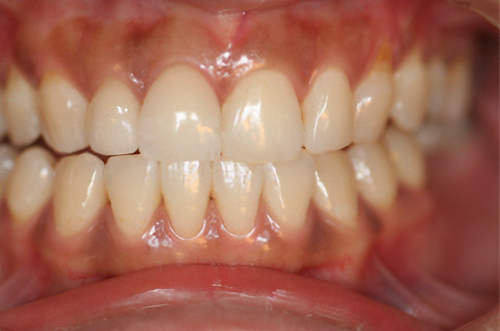

術後

黒ずんだ歯肉の色をお薬で、キレイなピンク色の歯肉にします。

塗り薬の麻酔と薬液だけで10分程度、2回の治療でキレイなピンク色に。-